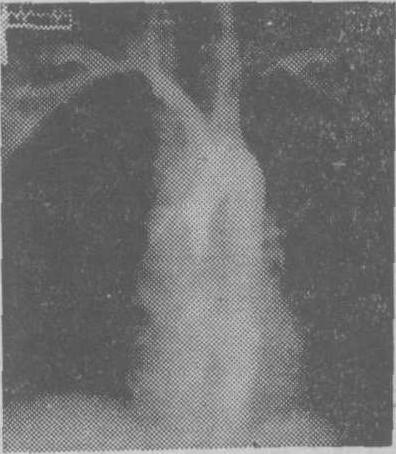

图1 胸主动脉造影

示左锁骨下动脉自乳内动脉开口以下完全梗阻,乳内动脉开口至椎动脉一段有狭窄。